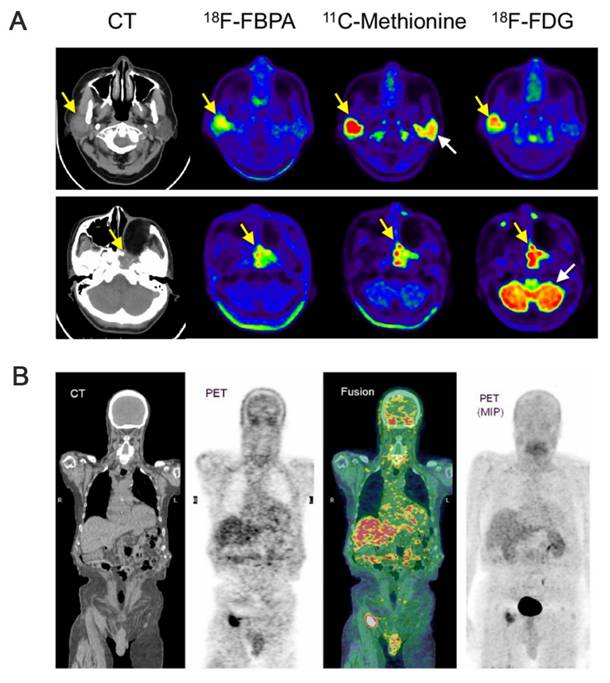

4. Visual evaluation of boron neutron-capture therapy